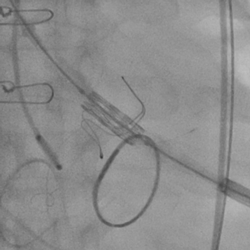

患者超声心动图:严重的主动脉瓣狭窄、二尖瓣返流

黄焕雷主任带领具有丰富经验的心脏麻醉医师、体外循环师、超声心动图医师、手术室、心外重症监护室、心脏导管室多学科团队,联合心内科专家谢年谨主任,为蔡先生实施小切口下、介入途径的主动脉瓣“瓣中瓣”、二尖瓣“环中瓣”的同期植入手术:黄主任首先在患者左前胸做一小切口,暴露患者的心尖,在跳动的心脏上“绣”上荷包作为介入导管、瓣膜的植入“门户”;随后,黄焕雷主任在超声心动图、放射透视的引导下,将一钢针在患者心尖“扎”入患者心脏内,为之后的瓣膜植入作为引导,具体来说就是将预先选择适合患者大小的生物瓣膜折叠、压缩入细长的输送管道内,好比将瓣膜这一“弹头”安放在输送导管这颗精准制导的“火箭”上,而黄主任的双手则控制这一精准发射和制导,再将瓣膜输送到主动脉合适的位置后释放,新的主动脉瓣便牢固地“卡”在了原有的主动脉瓣架内。经过透视和超声心动图评估,主动脉瓣位置合适,开放、闭合功能良好。随后,黄主任通过这一根钢针和输送导管,利用类似的方式,调整“火箭”的发射轨道,在原有二尖瓣人工瓣环内植入预先选择好大小的二尖瓣生物瓣膜,经过影像学方式评估,新植入的二尖瓣生物瓣工作良好。